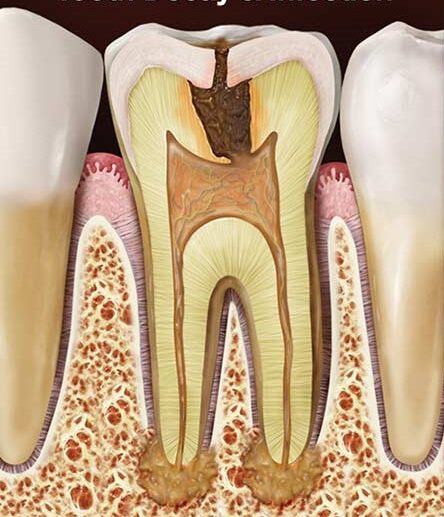

• nagy kiterjedésű fogszuvasodás és ennek következtében kialakult gyulladás

Gyökércsúcs rezekció

Gyökércsúcs rezekciót, a foggyökér csúcsának műtéti eltávolítását, olyan esetekben alkalmazzuk, amikor a gyökérkezelés valamilyen okból sikertelen. A gyökér végén fertőzés következtében kialakulhat ciszta. Sok esetben évekig tünetmentes lehet, röntgenfelvételen azonban kimutatható.

Vannak olyan esetek, amikor a gyökérkezelés kimenetele sikertelen.

Ennek több oka lehet:

• Fel nem tárt csatornák

• A gyulladás mértéke túl nagy, a szervezet nem képes egyedül megbirkózni vele

• A gyökércsatorna nem átjárható, így nem lehetséges a teljes kitisztítása

• A gyökértömő anyag nagy részben kikerült a gyökércsúcson kívülre

• Ha a kezelés során beletörne egy műszer a csatornába.